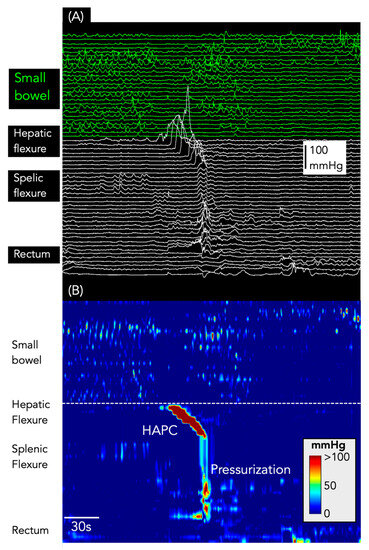

Figure 6.

Pressurizations following a HAPC. (A) shows the line plot of the manometry from the small bowel (green) and colon (white). (B) shows the same data shown as a spatiotemporal colour map.

Pressurizations were associated with 117 HAPCs (36%; Figure 6). Of these, 82 occurred after bisacodyl infusion, 27 occurred in association with HAPCs recorded during the basal period, and 10 occurred after a meal.

In addition to pressurizations, 188/327 HAPCs (57.4%) had SPWs pass through the propagating motor pattern (Figure 7). Every one of these SPWs also spanned all gastric and small bowel sensors (and the oesophagus, if sensors were present in that region: Figure 7).

Figure 7.

Simultaneous pressure waves associated with HAPCs. The X-ray image shows the placement of the catheter in the colon (white circles), small bowel (green circles), and stomach (red circles). The oesophageal sensors are not shown in the X-ray. (A) shows the line plot of the manometry. (B) shows the same data shown as a spatiotemporal colour map. Note that all SPWs span the stomach, small bowel, and colon and, in most instances, they are also detected by the sensors in the oesophagus. All of the SPWs are likely to represent body motion or abdominal strain (artefact) rather than genuine gut contractions.